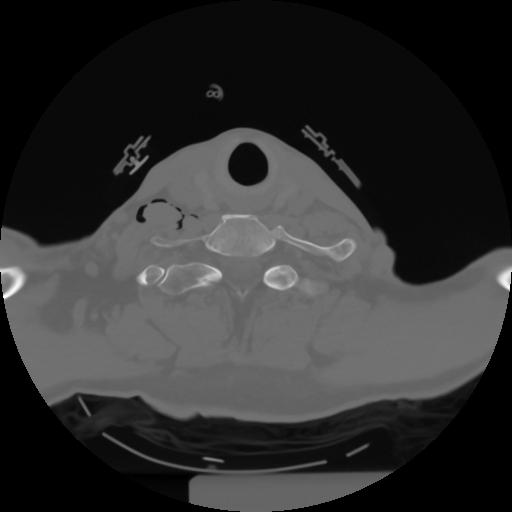

10 P.BLANDAS,,Axial,2.0,P.BLANDAS,,